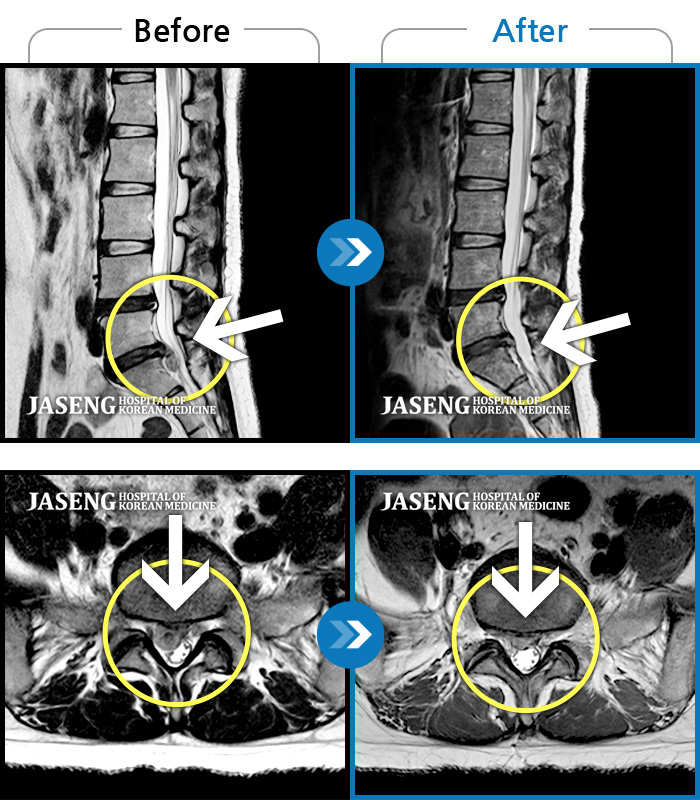

[뱸] 19.11.28~25.05.06